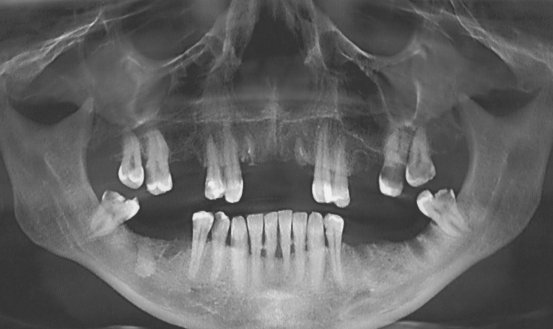

Здравствуйте! У меня вверху справа отсутствуют 4, 5, 6 зубы. А 2, 3 и 7-й депульпированы и подготовлены под протезирование. Какой протез можно поставить в данном случае? Сколько он будет стоить?

Добрый день. В вашем случае правильное решение - это, конечно, имплантация, альтернатива может быть только съемное протезирование. Вам необходимо посетить нашу клинику, так как протезов множество и они отличаются как по своей конструкции так и по цене.

Мостовидная конструкция в вашем случае противопоказана, слишком большой пролет.